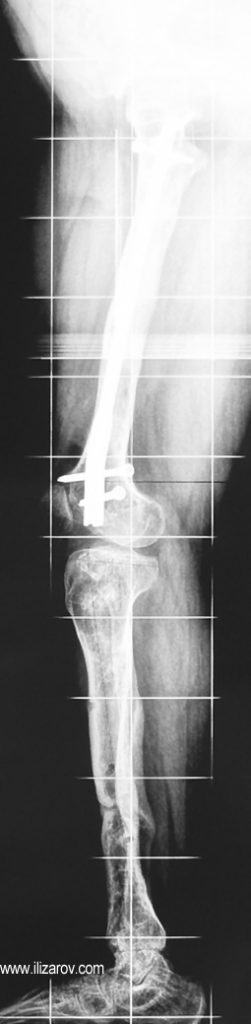

Hipofosfatemik raşitizmin neden olduğu bozukluk büyüme plağına çok yakın olduğu için büyük bir deformite ve ciddi dizilim bozukluğu ortaya çıkar. Bu nedenle cerrahi öncesi değerlendirmede sıklıkla birden çok deformite merkezi (CORA) bulunur ve deformitenin düzeltilmesi için birden çok seviyeden osteotomi yapılması gerekir. Deformitenin düzeltilmesi için en sık kullanılan yöntemler Ilizarov yöntemi ya da monolateral eksternal fiksatör kullanılarak akut ya da tedrici deformite düzeltilmesidir. Kliniğimizde uygulanan fiksatör yardımlı çivileme yönteminde deformite eksternal fiksatör kullanılarak akut olarak düzeltildikten sonra intramedüller çivi ile stabilizasyon sağlanmakta, uzatma yapılmayacaksa eksternal fiksatör cerrahi sona ermeden çıkartılmakta, uzatma yapılacaksa (çivi üzerinden uzatma) uzatma tamamlandıktan sonra fiksatör çıkartılmaktadır. Bu sayede tel dibi enfeksiyonu riski ortadan kalkmakta, hipofosfatemik raşitizm tedavisinde önemli sorunlar olan koreksiyon kaybı ve deformite nüksü önlenmekte, hastaya erken hareket verilerek tam yükle yürümesine izin verilmekte ve eksternal fiksatör süresi azaldığı için hasta konforu artmaktadır.

Vaka 4